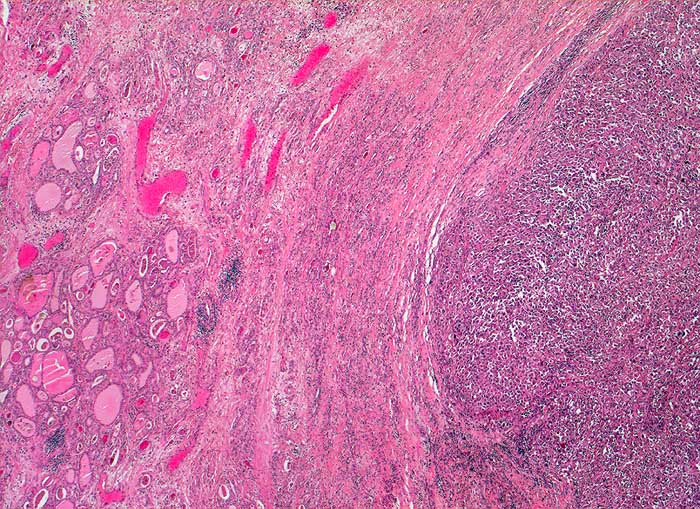

PathoPic ID 5460 - Anaplastisches Schilddrüsenkarzinom

Anaplastisches Schilddrüsenkarzinom

maligner Tumor

Schilddrüse

Endokrinium

Zwischen Schilddrüsenparenchym und solidem

Tumorknoten liegt eine dicke bindegewebige Kapsel. Bereits in dieser Vergrösserung ist erkennbar, dass der Tumor weder follikuläre noch papilläre Strukturen enthält.

Strumaknoten links mit Einengung der Trachea

Histologie

25